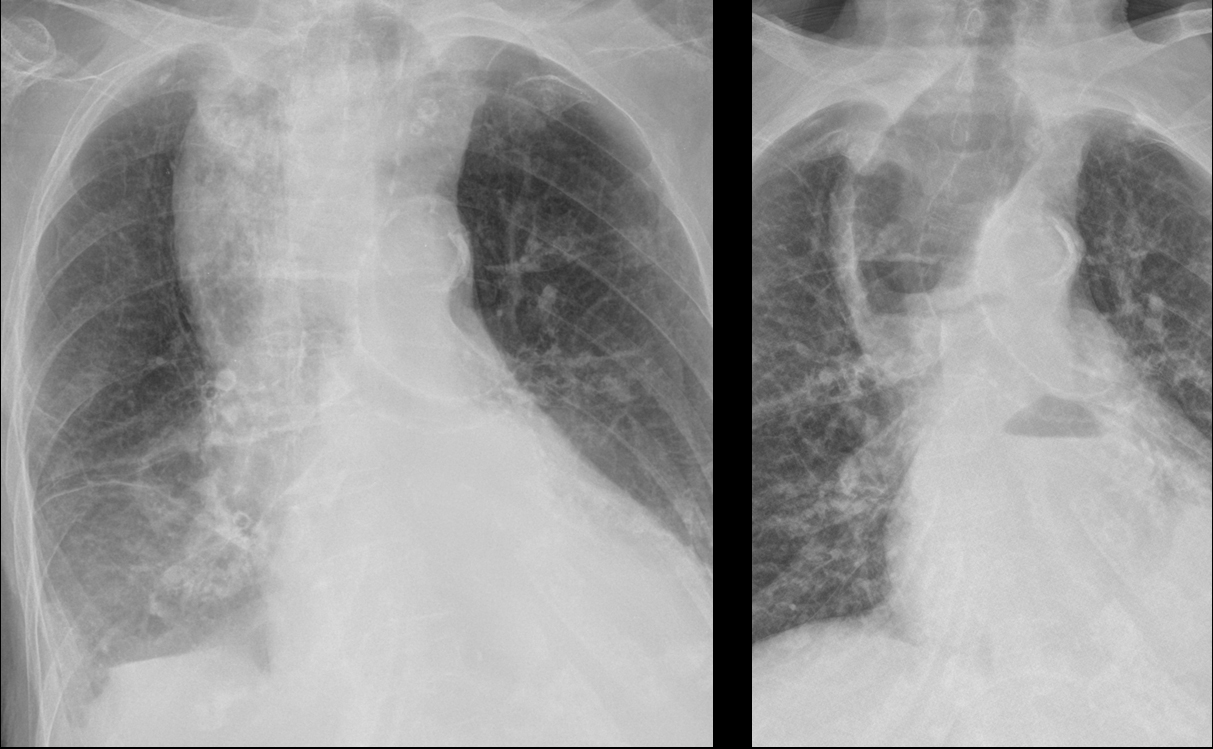

Gallery Mediastinum Miscellaneous Same patient PA views

Same patient  PA views